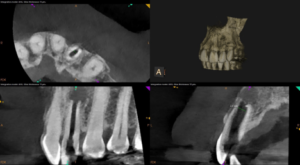

Our patient, a 57-year-old physician, came to us with a tooth that had likely experienced trauma when he was just seven or eight years old. Despite having undergone endodontic treatment in his youth, the tooth presented with some concerning issues:

- An apical lesion (an area of infection at the root tip)

- Immature root form

- Unusual placement of the previous treatment’s access filling